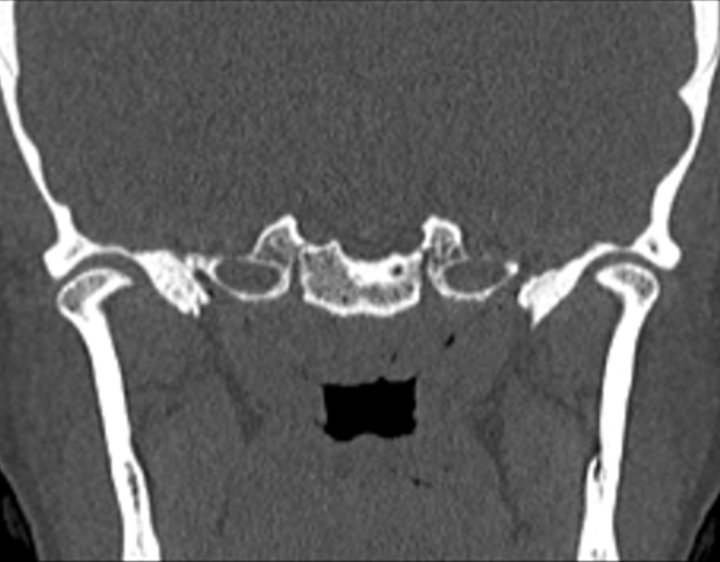

Click any image for labels.